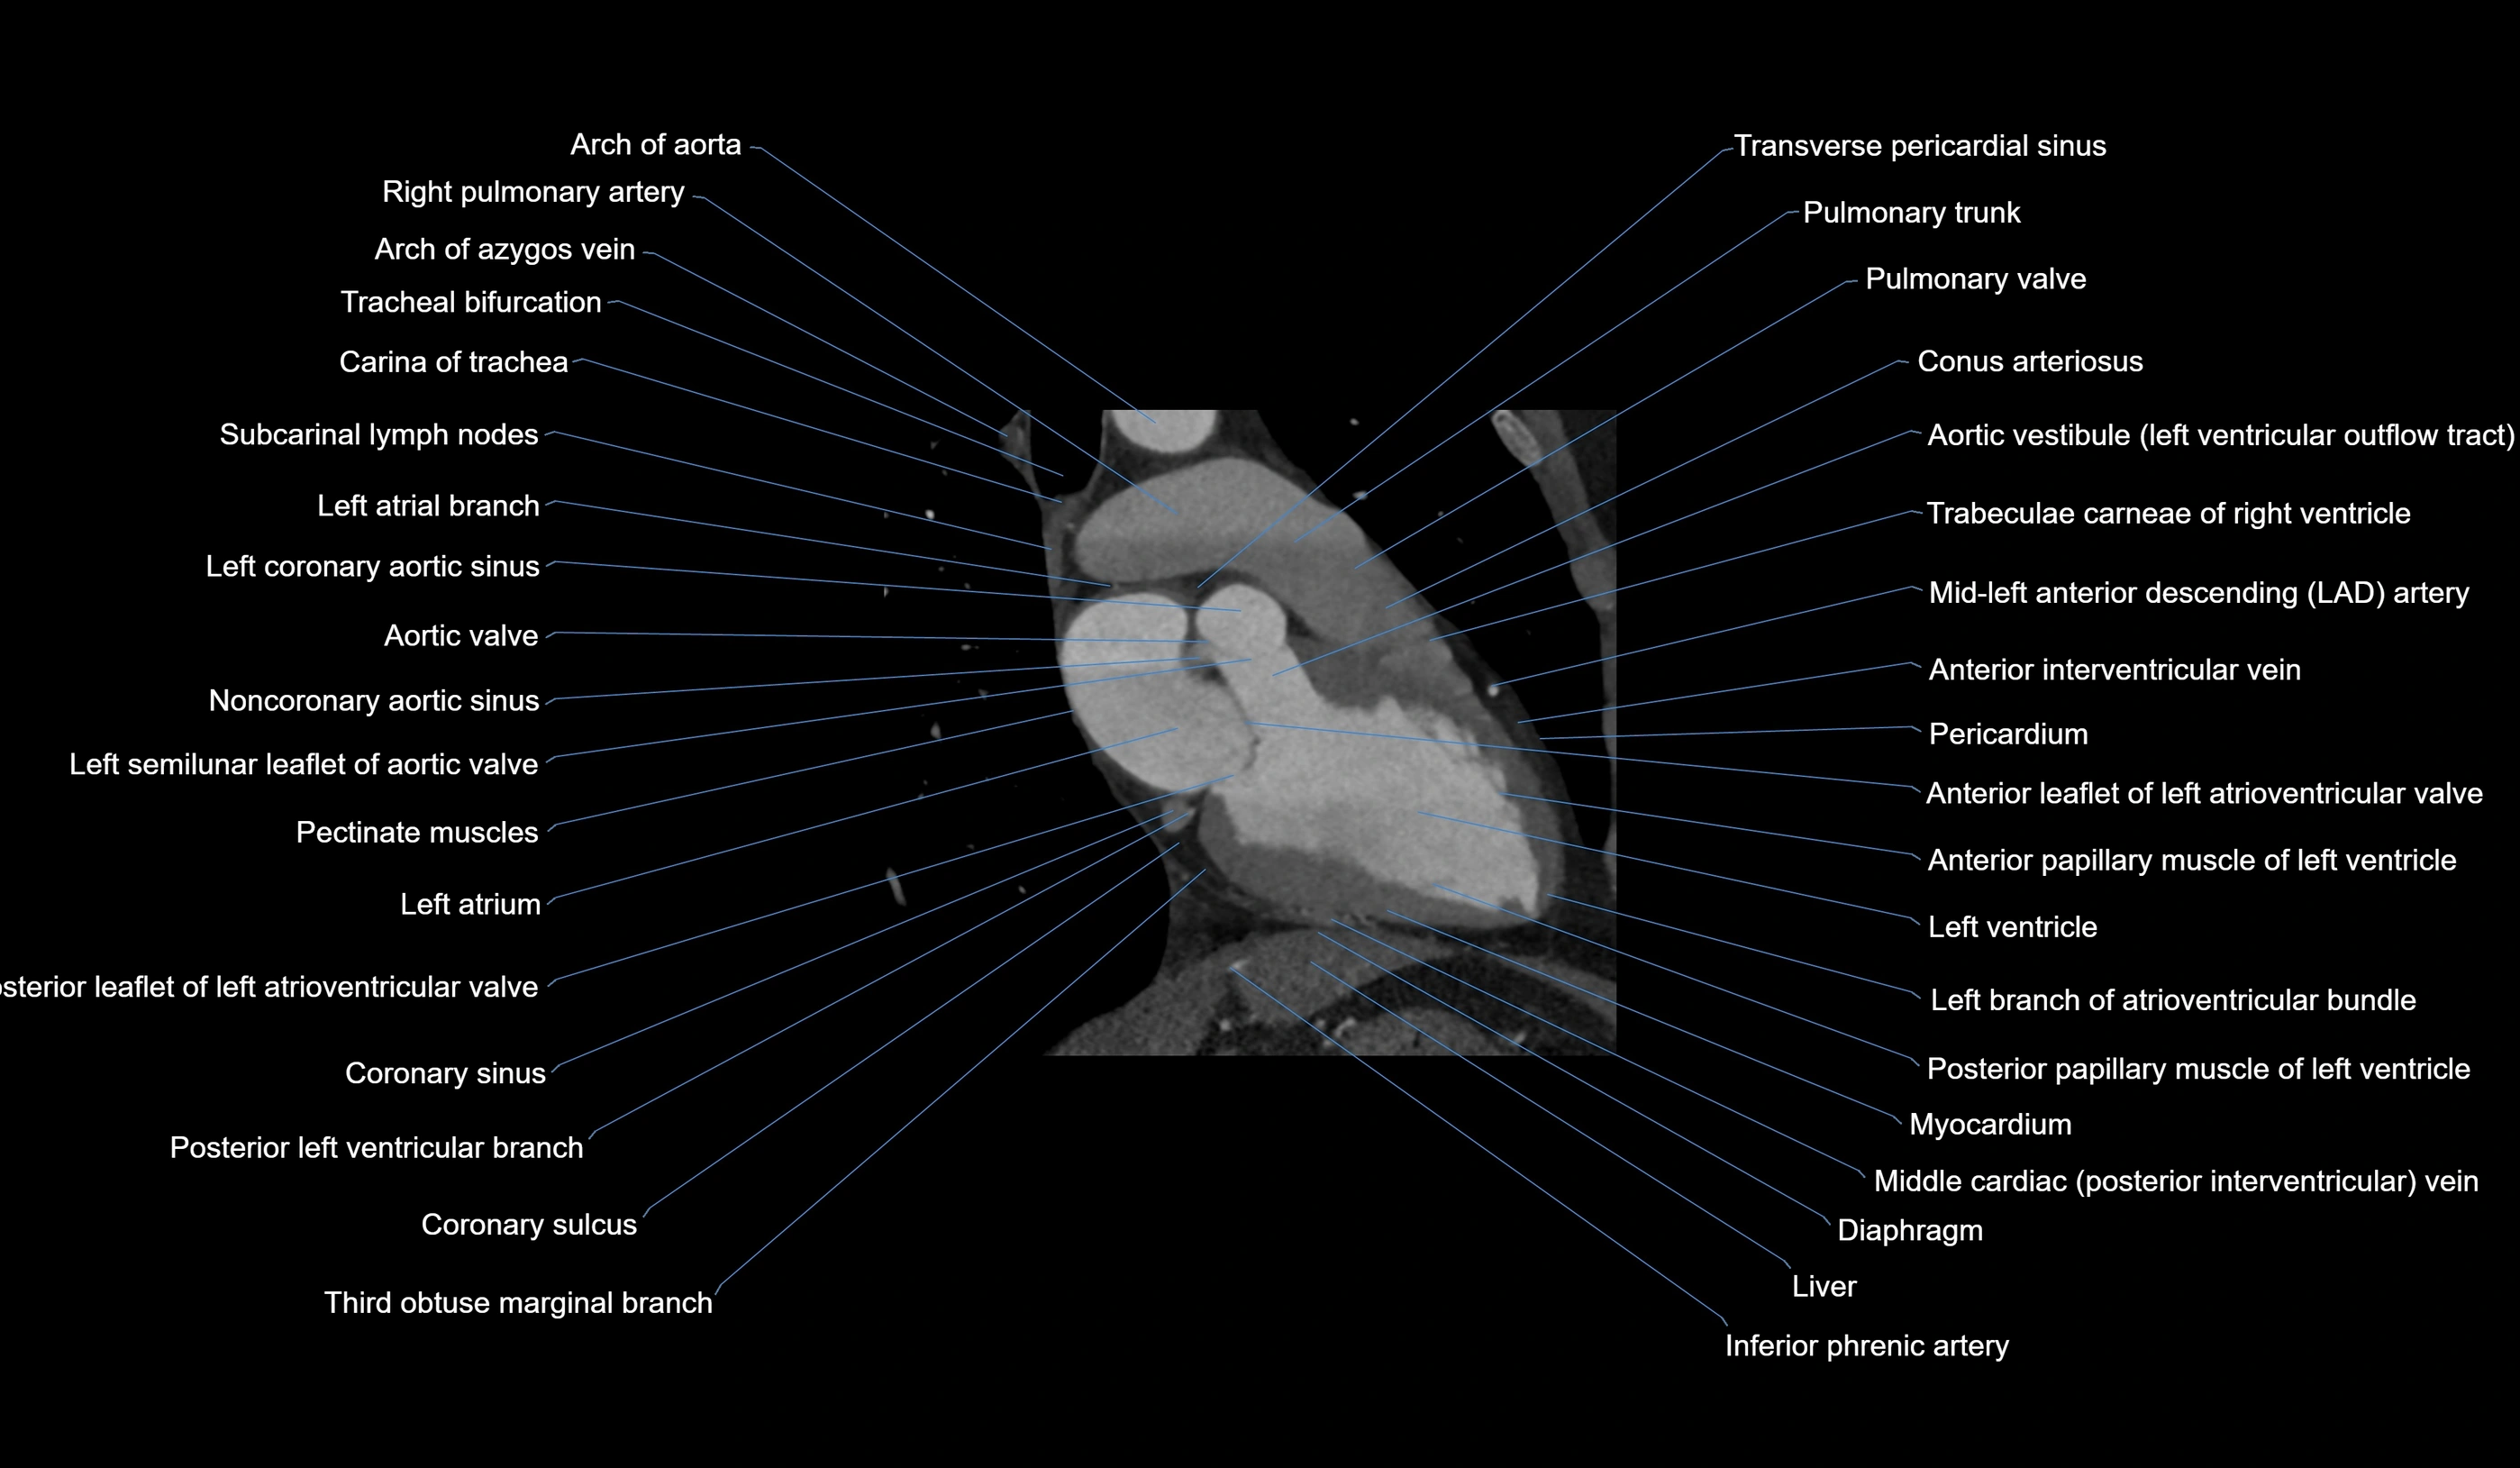

CT images